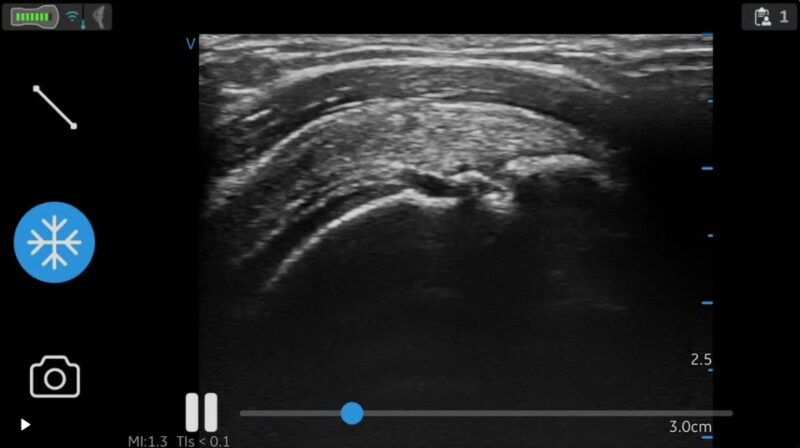

📷 エコー検査(超音波検査)を使うこともあります

必要に応じて、

エコー検査(超音波検査)を行います。

エコーは、

音の反射を使って筋肉やじん帯、すじの状態を画面で見る検査です。

• レントゲンのように放射線は使いません

• 小さなお子さまにも使える検査です

※エコーは病名を決めるための検査ではありませんが、

「今、どんな状態なのか」を知るための大切なヒントになります。

画面を一緒に見ながら説明しますので、

「よくわからないまま施術が始まる」ということはありません。